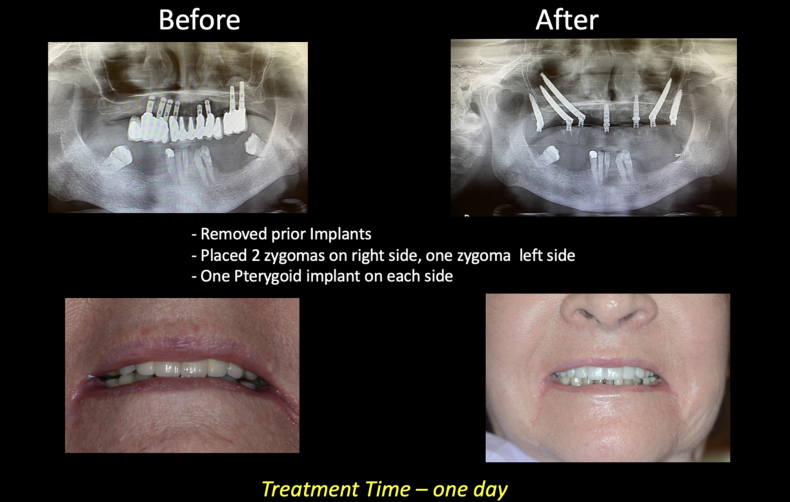

Case #2